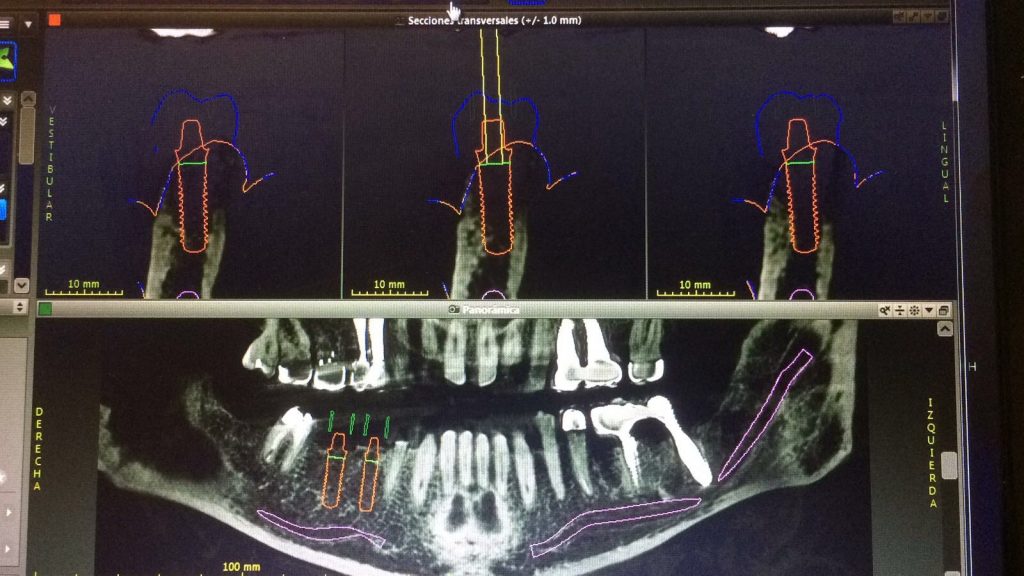

Autores: PRÓLOGO Asimismo, desde el punto de vista pedagógico, el profesional nobel en la materia tiene a su alcance la posibilidad de corregir cualquier posición implantaría en el ordenador, planear los provisionales y plasmarlos en la bio réplica antes de tocar al paciente a operar. Todos estos razonamientos nos llevan a presentar un caso de condiciones muy favorables para poner en práctica estos métodos como primer acercamiento a una Odontología Digital de alta calidad, con medios informáticos, que ya están presentes en la profesión de hoy en día, y será la protagonista única del futuro. Por otro lado, después de numerosos estudios que nos llevan a plantear el “gap” entre implante y pilar(abuttment), como principal responsable de la periimplantitis dado que la microbiota presente en el mismo es imposible de limpiar y en su presencia la cortical ósea reacciona reabsorbiéndose, nos ha llevado a utilizar implantes monobloc ya que los ejes implantarios y protéticos coincidían, y nos permitían su uso. Además, el circonio, ha mostrado a la luz de estudios muy recientes, una preservación y adhesión de los tejidos blandos superiores al titanio, tanto en su tratamiento de superficie de la rosca como a nivel gingival. DESARROLLO Paciente varón de 68 años, con antecedentes de radio/quimioterapia cinco años antes, con Rehabilitación Oral de los cuatro cuadrantes, con una Oclusión Mutuamente Compartida conservada, (REF.8) la que fracasa en el cuadrante 4, 19 años después. El mismo presentaba un puente de porcelana sobre circonio con pilares en 44 y 47, reemplazando el edentulismo de 45 y 46. Se produce la fractura del PM del 44, y ante una endodoncia antigua y corta, se decide implantar las zonas edéntulas, conservando temporariamente los pilares, hasta producida la oseointegración, para entonces también exodonciar el 44. DIAGNÓSTICO Tomamos impresiones del maxilar antagonista, Arco Facial Estático y realizamos montaje del mismo mediante la sistemática ARTEX. Producimos la relajación del músculo Pterigoideo Externo, para obtener la ORC (Oclusión en Relación Céntrica) mediante el método de Laminillas de Long, basado en el concepto de INERVACIÓN RECÍPROCA. Esto nos permitirá montar el maxilar inferior, tanto en su forma de: La primera para practicar la cirugía guiada y comprobar su eficacia, y el modelo de yeso para ser escaneado y confeccionar la GUÍA QUIRÚRGICA. La Biorréplica la obtenemos transformando los archivos DICOM que nos da el CBCT en archivos STL, y a partir de ellos, mediante una tecnología de PROTOTIPADO RÁPIDO, la obtención de un objeto físico en 3D a través de la aglutinación selectiva de una sucesión de capas de polvo. Procedemos a montar la biorrèplica y el modelo de yeso del caso. Podemos verificar la exactitud de las medidas del hueso residual en la bio réplica y compararlas con el scanner. Arrojando un resultado de 8,5 mm de cortical externa a cortical externa. Pudiendo también medir la distancia hasta el dentario. y comparar gracias a la ventana lateral de la biorréplica Dándonos 22mm de distancia. Con lo cual deducimos que implantes de 4,1mm por 12 mm serán perfectamente rodeados de hueso. Medimos también la distancia desde oclusal del antagonista, hasta el hueso desnudo. Lo mismo que, mediante la utilización de la guía radiológica, con un material radiolúcido colocado en gingival de la misma, podemos medir la altura de la encía. Con lo cual podemos calcular la altura del pilar. Es entonces cuando con el programa COC Diagnostix se realiza la programación final: Obteniendo no solo la ubicación, largo, ancho y ángulo de los implantes sino también los provisionales mediante CAD CAM. Ya entonces podemos hacer la práctica quirúrgica en la bio réplica, mediante la guía quirúrgica, instalando los implantes de prueba que no serán los de circonio, ya que la casa no cuenta con ellos, pero si otros de las mismas dimensiones. TRATAMIENTO Entramos ya en la cirugía propiamente dicha. Antisepsia de la zona a operar y zonas anexas. Comprobación del perfecto ajuste e inmovilidad de la G.Q. en boca durante la cirugía. Marcado de la encía y perforación de la cortical. Visión a través de la Guía de la mínima intervención anterior. Comprobación sin Guía. Incisión mínima mesio distal, para apartar y conservar encía queratinizada. Secuencia de drills, perforando a profundidad requerida Observación del Mínimo Trauma Implantes Strauman de Zirconio Monoblock en blíster y montádo en contrángulo reductor. Instalación controlando torque con contrángulo reductor. Comprobación clínica. Comprobación Radiográfica y con Guía. Toma de impresiones, y armado de modelos con técnicas de pasividad protética. Montaje. Resultado de las provisionales ejecutadas por CAD CAM Al no estar conformes con el resultado decidimos desechar dichas provisorias y optar por repetirlas. Nuevas provisorias realizadas mediante encerado convencional. Estado de los tejidos blandos. Provisorias en boca. Oclusión de Estímulo Inmediato. Ref.10: Carga inmediata .Alberto y Diego Bechelli. Comprobación mediante CBCT post operatorio Componentes del equipo (En la próxima presentación, mostraremos las coronas definitivas de porcelana sobre circonio, y la desoclusión provocada por una OCLUSIÓN MUTUAMENTE COMPARTIDA, sobre estos implantes y otros seis mas) REFERENCIAS

Realizamos previamente una Rx periapical Dígora (radiovisiografía) y un CBCT (TAC de haz de cono) con férula radiológica, marcando ambas raíces del 46 y la raíz del 45.

FIG: 5-6-7-8

FIG: 9-10-11-12

FIG: 14-15-16-17-18-19-20

FIG: 21-22-23-24-25-26

Fig. 21

Fig. 22

Fig. 23

Fig. 24

Fig. 25

Fig. 26